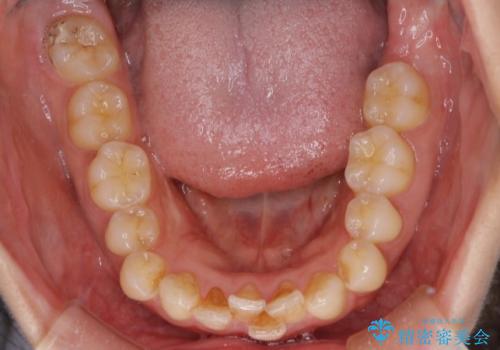

- 下顎前歯の叢生を主訴に来院されました。

臼歯関係の状態から下顎前歯一本の抜歯を行う治療計画を立て、インビザラインを使用して治療を行いました。

今回の抜歯ケースはインビザラインでも綺麗に治ります。